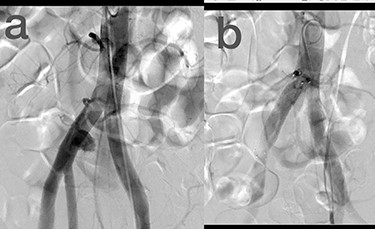

Sites of injury included 6 Posterior Tibialis arteries (27.2%) (Fig. 1), 2 deep femoral arteries (9.09%), 2 Superficial femoral arteries (9.09%) and 2 maxillary arteries (9.09%). We had only one injured artery (4.54%) in each of the following sites: internal pudendal a., Axillary a. (Fig. 2), Proneal a., Lumbar a., External carotid a., Anterior Tibialis a., common iliac a. (Fig. 3), temporal a., Thoracic aorta and Internal iliac artery (Fig. 4).

(a) Posterior Tibialis artery before intervention, (b) after endovascular stent graft deployment.